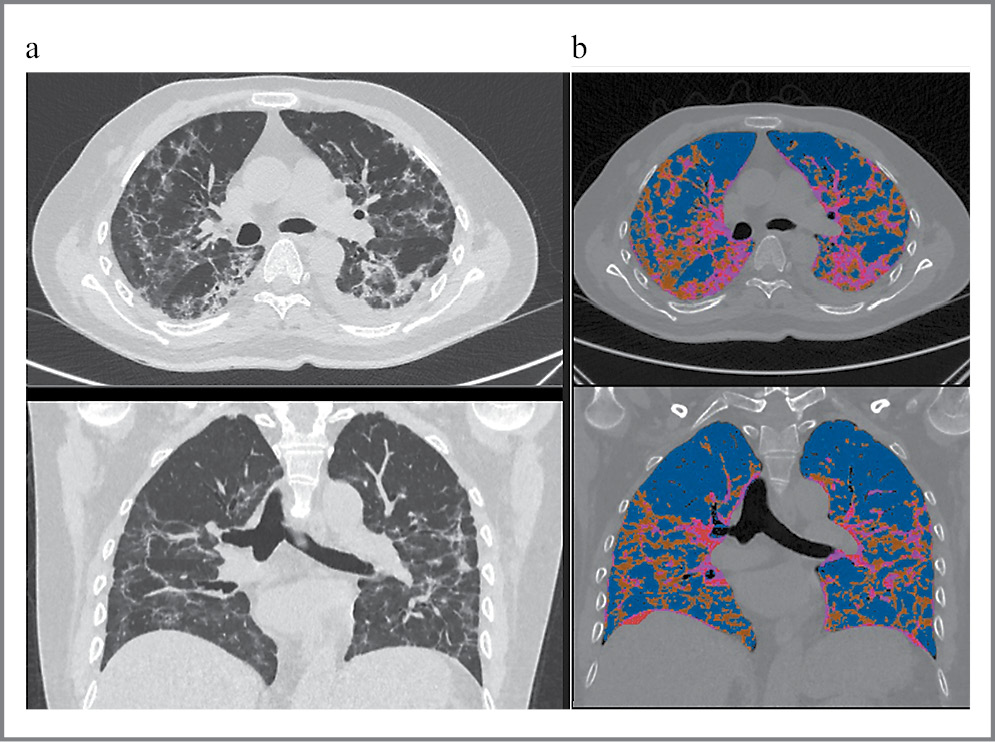

При анализе КТ-картины у пациентов, обратившихся в стационар в сроки с 61 по 180-й день после выписки, отмечалось снижение доли патологически измененных зон до 19,7%. Из них «матовое стекло» занимало 8,8%, консолидация – 1,3%, а ретикулярные изменения – 9,4% (табл. 3).

| Таблица 3. Оценка патологических паттернов при выполнении КТ ОГК в разные сроки после выписки из стационара Table 3. Evaluation of pathological patterns during CT of the chest circumference at different times after discharge from the hospital | |||

При динамическом наблюдении мы можем видеть явное уменьшение патологических зон, причем чем в более поздние сроки выполнялось динамическое КТ-исследование, тем меньший объем патологически измененной ткани фиксировался (рис. 7).

Рис. 7. Динамические изменения по данным КТ ОГК в стационаре, ранние и отдаленные сроки после выписки из стационара.

Важно отметить, что регресс патологических зон у пациентов после перенесенной тяжелой коронавирусной пневмонии – это процесс постепенный, и может занять от нескольких недель до нескольких месяцев.

Наше исследование показывает, что при оценке КТ легких в динамике у всех пациентов наблюдался не только значительный регресс патологических изменений, зависимый от удаленности эпизода коронавирусной пневмонии, но и трансформация патологических зон из «матового стекла» и консолидатов преимущественно в ретикулярные изменения (рис. 7).

Наши данные по мониторингу динамики КТ-изменений подтверждают уже ставшую общепризнанной концепцию об отсутствии формирования значимых фиброзных изменений в легких у пациентов после коронавирусной пневмонии.